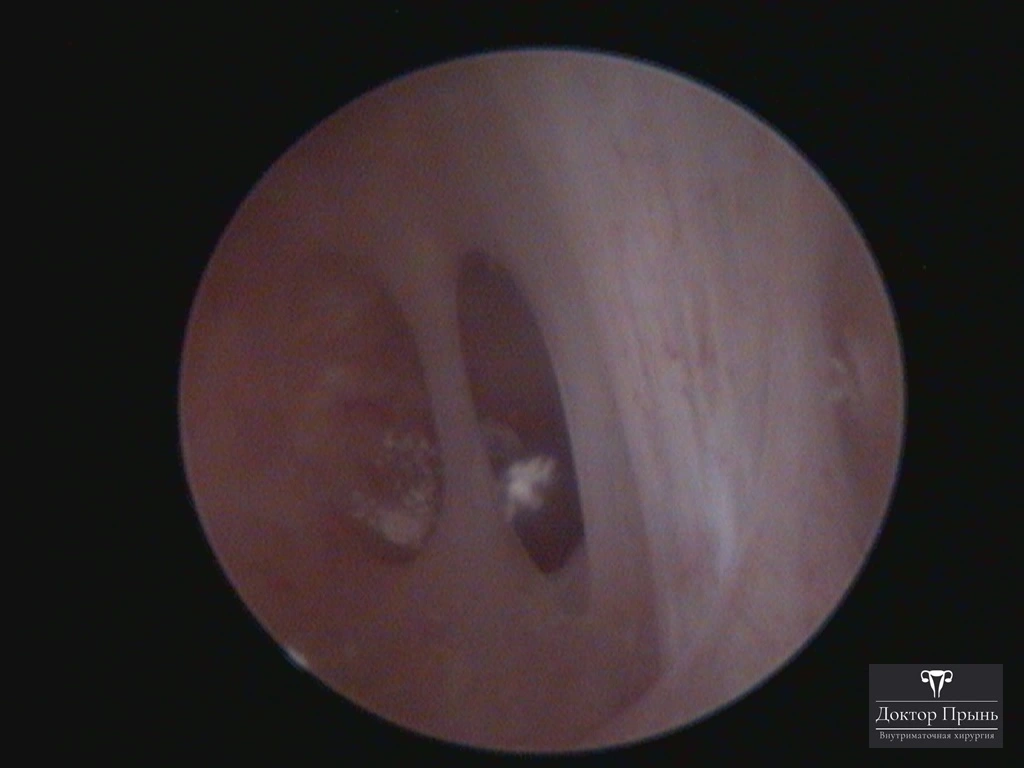

Как правило, синехии находят при УЗИ. Когда по УЗИ патологии нет, а симптомы есть, выполняют гистероскопию – это золотой стандарт в определении синехий.

Гистероскопия позволяет не только увидеть спайки, но и сразу вылечить, т.е. рассечь их. Большинству пациенток подойдёт офисная гистероскопия без наркоза и госпитализации. Среднее время операции 15 минут. Иногда требуется 2-4 операции, чтобы восстановить полость матки.

Крайне важен способ разделения спаек. Если это холодный инструмент, например, ножницы, то вероятность рецидива низкая. Плюс не повреждается нормальный эндометрий. Если рассекают горячей электропетлёй, то, наоборот, риск рецидива высокий и можно обжечь эндометрий.

Синехии, рассечённые Прынь Д.В.